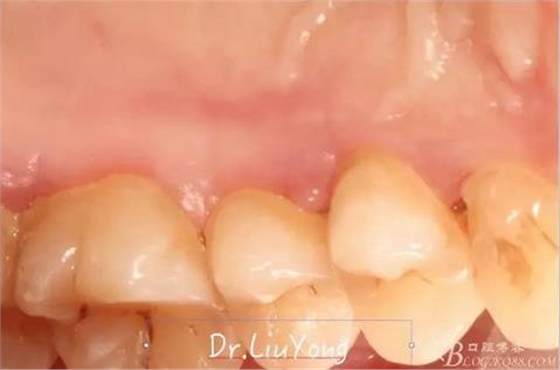

潔治刮治后2周,如上圖

術后兩周復查,牙齦紅腫明顯好轉,探診不出血,但是此時A1唇側牙齦角形退縮1.5mm,B1唇側牙齦退縮3.5mm,B1遠中牙齦乳頭萎縮明顯,B2近中牙齦萎縮約1mm,且A1B1B2牙齦退縮處角化牙齦幾乎缺失,同時上唇系帶直接牽拉于B1齦緣。患者為高笑線女性,露齦笑,由于存在前牙區(qū)牙齦的高度嚴重不對稱及前牙牙冠過長的問題,因此嘗試通過膜齦手術改善患牙牙齦退縮。通過術前分析,A1唇側牙齦退縮屬于Miller分類第一類, B1唇側牙齦退縮屬于Miller分類第3類(B1遠中牙齦乳頭為2類,Nordland and Tarnow分類法),B2唇側牙齦退縮屬于Miller分類第3類,由于擬采用冠向復位瓣的方式治療牙齦退縮,因此需要先行上唇系帶修整術,解除上唇系帶帶來的過大牽引力。